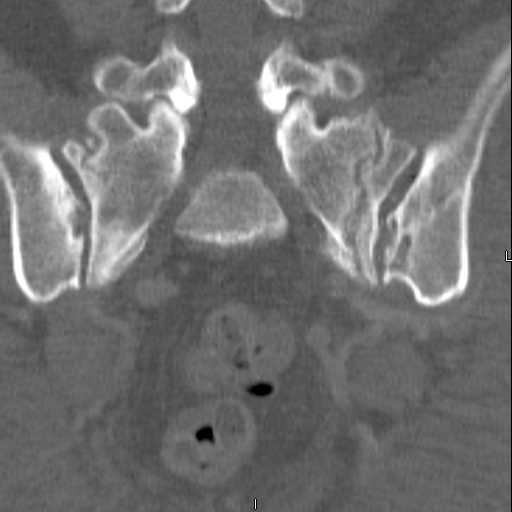

Here are a recent patient’s example slides...

54 yo Female Fell c/o Pain

Initial Films

?Instability on Exam - Limited by Pain

NonOp Initial Mgmt

3 Months After Fall

Continued Pain & Immobility

(+) Instability to Compressive Manual Exam

Pelvic CT Scan - 3 Months After Fall

Sacral Injuries

Ramus Fractures